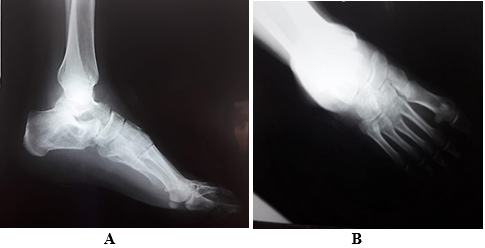

Standard chest x-ray: normal (Figure 1). Anteroposterior (AP) and lateral radiograph of the left ankle. Calcaneus with a delimited circular radiolucent image, with an increase in volume in the soft tissues (Figure 2). Laboratory studies showed positive CRP, increased RSV with lymphocytosis. A vascular Doppler echo of the left lower limb was performed due to the edema, which indicated no vascular compromises. The computed tomography of the left foot shows a hypodense osteological-type lesion, affecting two-thirds of the calcaneus, thinning of the cortices and involvement in the support area of the calcaneus (Figure 3).

Figure 2A Lateral x-ray of left foot shows the calcaneal bone in a delimited circular radiolucent image.

Figure 2B AP x-ray of the left foot shows an increase in volume in the soft tissues.